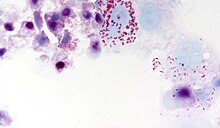

Diplorickettsia massiliensis grown in XTC-2 cells, Gimenez staining

Basic fuchsin stain in aqueous solution with phenol and ethanol colours many bacteria (both gram positive and Gram negative) red, magenta, or pink. A malachite green counterstain gives a blue-green background cast to the surrounding tissue.